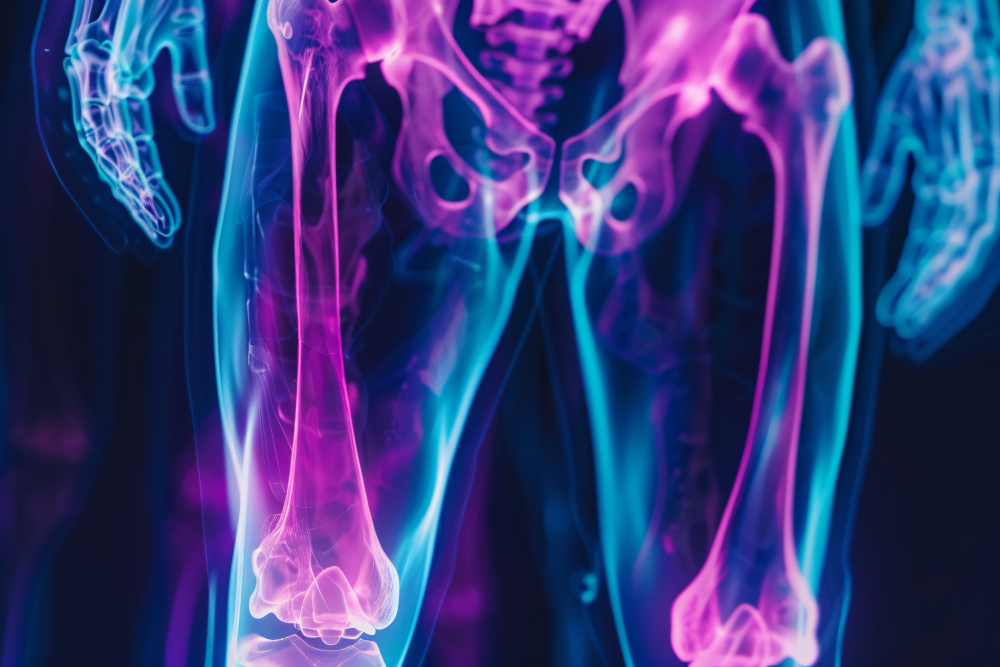

Множественный остеохондроматоз или множественная экзостозная хондродисплазия - это заболевание, которое может передаваться по наследству. Выражается оно в образовании многочисленных хрящевых новообразований (остеохондромы) и деформациях конечностей. По статистике множественный остеохондроматоз наблюдается примерно у 1 человека из 50000 и в 90% случаев имеет место мутация генов EXT 1 или EXT 2.

- Появление многочисленных новообразований костной плотности в разных областях: нижние и верхние конечности, позвонки, ребра, таз, лопатки.

- Наличие деформаций верхних и нижних конечностей.